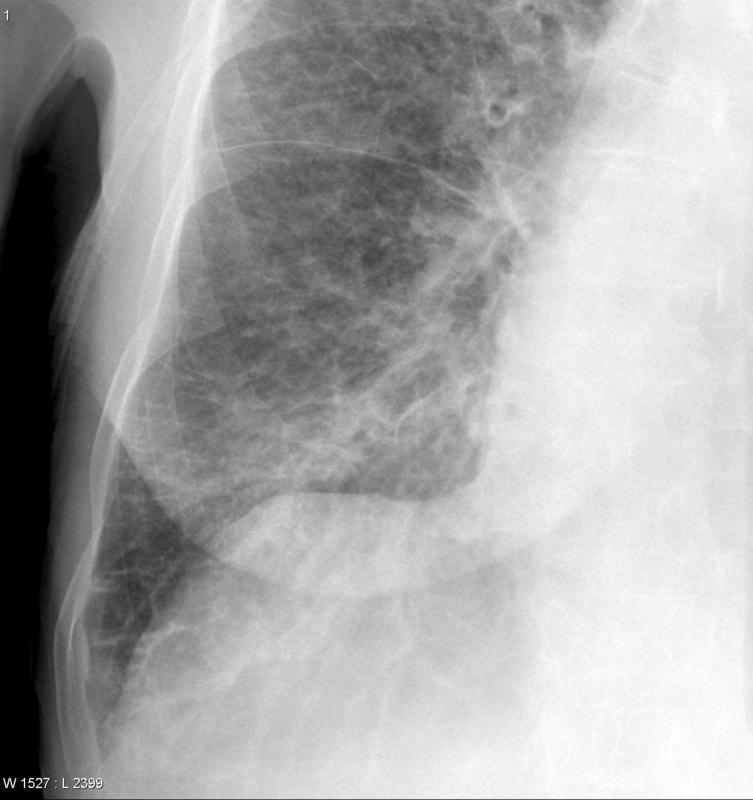

Gallery Cardiac Heart failure septals

septals